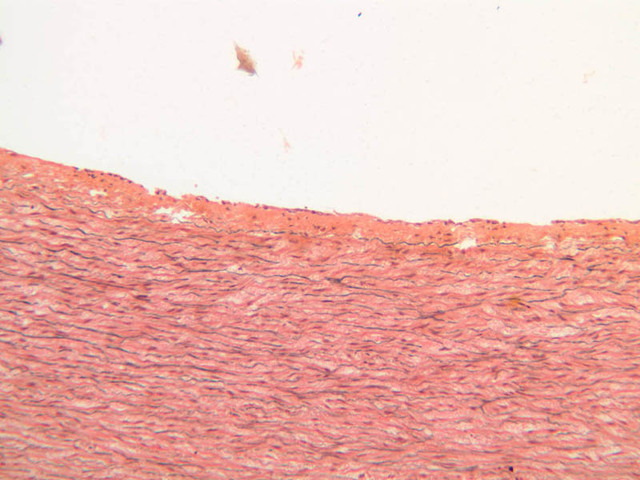

The blood is pumped from the heart into large, elastic (conduction) arteries. Examine a section of the aorta (A-26, H&E [2.5x, 10x, 20x, 40x-labeled] [2.5x, 10x-labeled, 20x, 40x]) which is a typical elastic artery. Although the tunica intima and tunica media are difficult to distinguish, note that together they are much thicker than the tunica adventitia. Using high power magnification, examine the tunica media and identify the cell types and fibers, recalling that elastic tissue appears light pink and refractive in H&E preparations. Compare this slide with a section of aorta stained to demonstrate elastic fibers (A-27, verhoeff [2.5x, 10x, 20x, 40x-labeled] [2.5x, 10x]).

Note how extensive the elastic tissue is in the tunica media. The elastic tissue is arranged in the form of numerous concentric elastic lamellae, which are cross connected by slender elastic fibers. Observe the distribution of elastic fibers in the tunica intima (A- 27 [2.5x, 10x, 20x, 40x]) and tunica adventitia (A-27 [10x, 20x, 40x]). The internal and external elastic membranes are not well demarcated in the aorta since so many elastic lamellae are present. The elasticity of the aorta allows it to expand and absorb much of the pressure during contraction of the left ventricle (i.e., systole). When the ventricle relaxes (diastole), the elastic aorta contracts, continuing the movement of blood into the medium and muscular arteries.